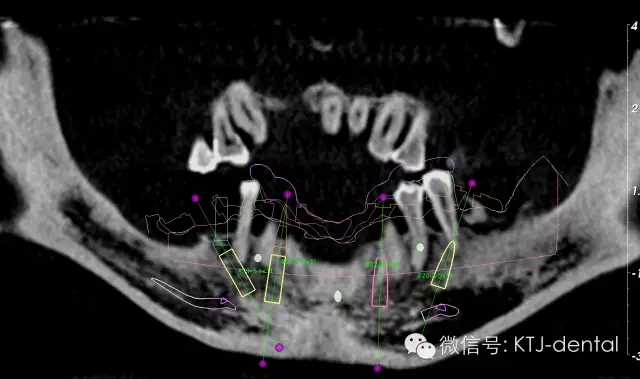

圖2 曲面斷層全景圖

圖3-4 三維立體顯示設計圖

本病案小結(jié):使用預成種植套筒冠基臺行無牙合即刻負重手術(shù)操作簡單,效果可靠,臨床應用方便快捷。但種植體的平行度是保證此修復方式成功實施的關鍵。本病例的CAD CAM手術(shù)導板在應用過程中發(fā)揮以下作用:嚴格控制種植體的平行度,避免損傷下牙槽神經(jīng)及頦神經(jīng)(無須翻瓣暴露神經(jīng)),根據(jù)種植體植入深度預選適當?shù)幕_,根據(jù)術(shù)前打印模型預先調(diào)磨即刻負重義齒。CAD CAM手術(shù)導板的應用使得手術(shù)操作有更強的預期性。在應用技巧方面,預先保留不影響植入位點的牙齒,獲得更為精確的牙支持式的手術(shù)導板,減少了手術(shù)誤差。半程導板配套的器械盒應該合理地與相應種植系統(tǒng)外科器械配合使用,并根據(jù)骨的質(zhì)地采用相應的預備方式,使得植入位點精確,并獲得良好的初期穩(wěn)定性完成下一步的即刻負重治療。